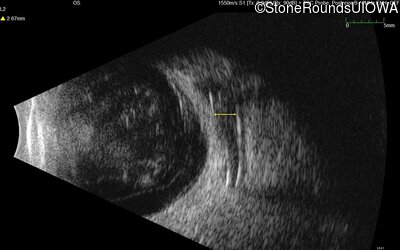

Visit at age: 37 years

B-Scan Ultrasonography - Right - Light Perception

Exemplar